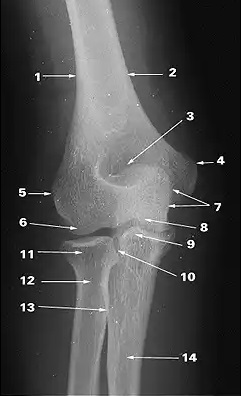

What does 2 indicate?

medial supracondylar ridge

What does 1 indicate?

lateral supracondylar ridge

What does 3 indicate?

olecranon fossa

What does 4 indicate?

medial epicondyle

What does 5 indicate?

lateral epicondyle

What does 7 indicate?

olecranon

What does 8 indicate?

trochlea

What does 10 indicate?

proximal radioulnar joint

ulna

radius